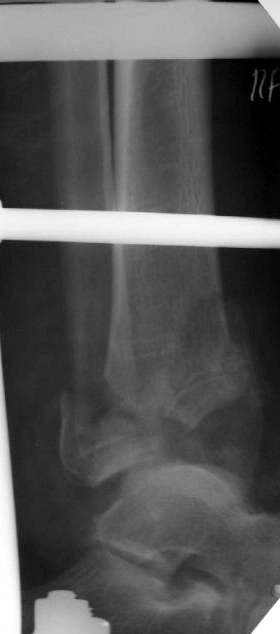

Перелом 43С

Поступил больной 57 лет 14.06.04 в наше отделение.Простой перелом малоберцовой кости Взрывной перелом дистальных отделов болыпеберцовой кости,

Вколоченный перелом дистальных отделов большеберцовойкости.Проводим репозицию с помощью скелетного вытяжения, перед операцией. Думаем как собрать б/б кость? Какой доступ использовать? Может сразупервичный артродез?Как то в форуме говорилось о доступе через м/б кость для артродеза. Возможноли его использовать в данном случае?Если кто-то его использует, может поделится информацией, как правильно егоделать?Сергей ЗыряновНСО г Куйбышев.ЦРБ

Судя по снимкам - нет.